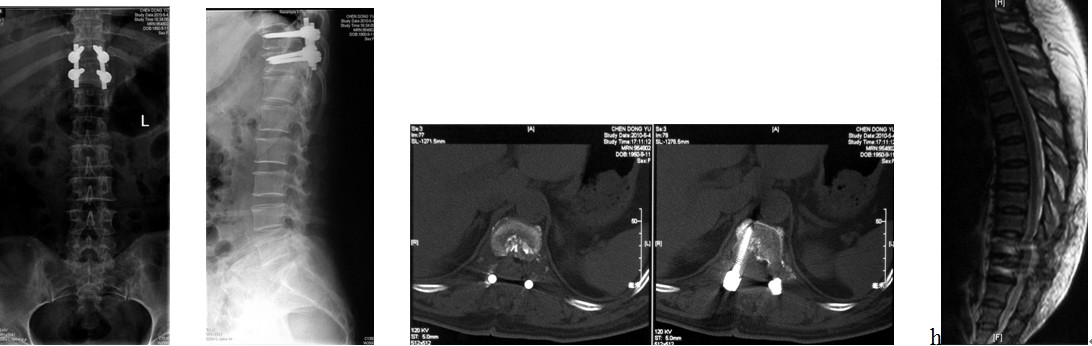

4. 典型病例:病例1,患者男性,40岁,司机。主因胸腰背部疼痛3年,肛周麻木、性功能减退并伴双足下垂2年,症状加重且二便肥力、无法工作1年入院。入院查体:一般情况良好,体胖、体重105kg。步态不稳,步行缓慢。胸腰段脊柱背部轻压痛,无放射。双侧股四头肌力IV级,双侧胫前肌力I级,双侧足下垂。鞍区感觉减退,无病理征。双侧跟、膝腱反射消失。血化验检查正常。X线平片显示T12~L1椎间隙明显变窄。CT显示T12~L1椎间盘突出并椎体后缘离断。MRI显示T12~L1椎间盘呈中央型突出,椎管狭窄,脊髓明显受压变形。入院诊断:T12~L1椎间盘突出症伴椎体后缘离断,马尾神经损害。术前检查完成后,在气管插管全麻下行上述经极外侧入路T12~L1椎间盘切除手术治疗,整个手术过程顺利,无术中及术后并发症发生,术后1周顺利出院。出院时,其双侧股四头肌、胫前肌肌力已分别恢复至V级和III级;鞍区感觉减退亦有明显好转。术后显示T12~L1突出之椎间盘及离断之椎体后缘已被完全切除,椎间融合器及椎弓根螺钉位置佳,脊柱局部生理曲度良好(图2a~2l)。病例2,女性患者,59岁。主因间歇性跛行,双下肢无力3年入院。入院诊断:T11椎体后上缘骨软骨瘤。以与病例1相同的术式行椎体骨软骨瘤的彻底切除(图3a~3l),无手术并发症发生,术后患者下肢症状明显改善。

图2i~2l. 典型病例1患者术后X线片, CT显示突出之椎间盘及离断的椎体后缘已被彻底切除, 内固定和椎替间融合器位置良好.

图3i~3l. 典型病例2患者术后之线片, CT, MRI显示骨软骨瘤已被彻底切除, 脊髓获得充分减压, 内固定位置良好.